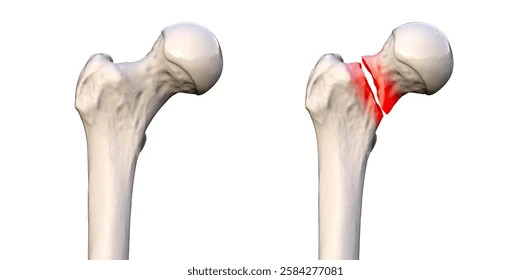

location of break

Femur Neck